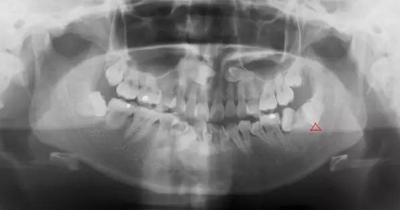

智齒遠(yuǎn)中阻生(遠(yuǎn)離鄰牙方向長)反復(fù)炎癥感染

2.jpg